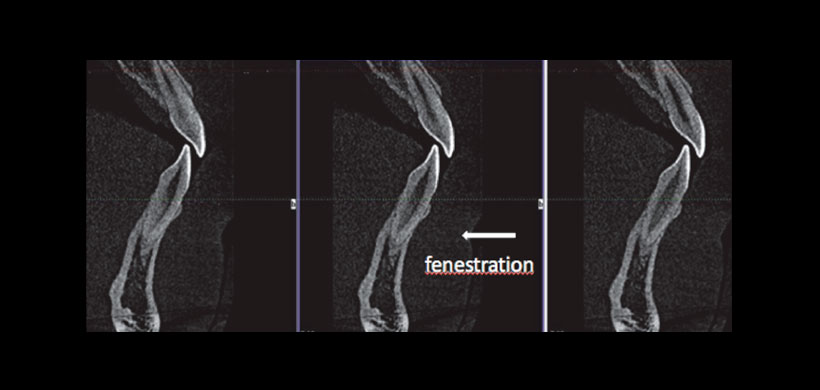

Figura 1: Fenestracion diagnosticada mediante CBCT

En general, se evaluaron 1.395 dientes. Las fenestraciones de raíz se identificaron de acuerdo con la definición de Davies y la Asociación Americana de Endodoncistas. (Figura 1)

Los defectos óseos como dehiscencias y fenestraciones son hallazgos comunes en la dentición natural, siendo más frecuentes en hueso vestibular que en el hueso lingual, y en el hueso de los dientes del sector anterior. Las fenestraciones son áreas aisladas en las que se encuentran las raíces desnudas de hueso y las superficies de raíz están cubiertas solo por periostio y gingiva suprayacente, pero el hueso marginal está intacto.